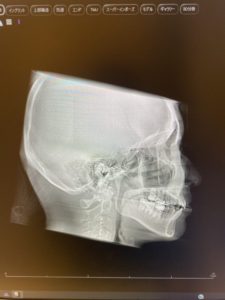

✅ 定期的にレントゲンで確認

👉 途中で根の変化が見られた場合、矯正計画を調整できます。